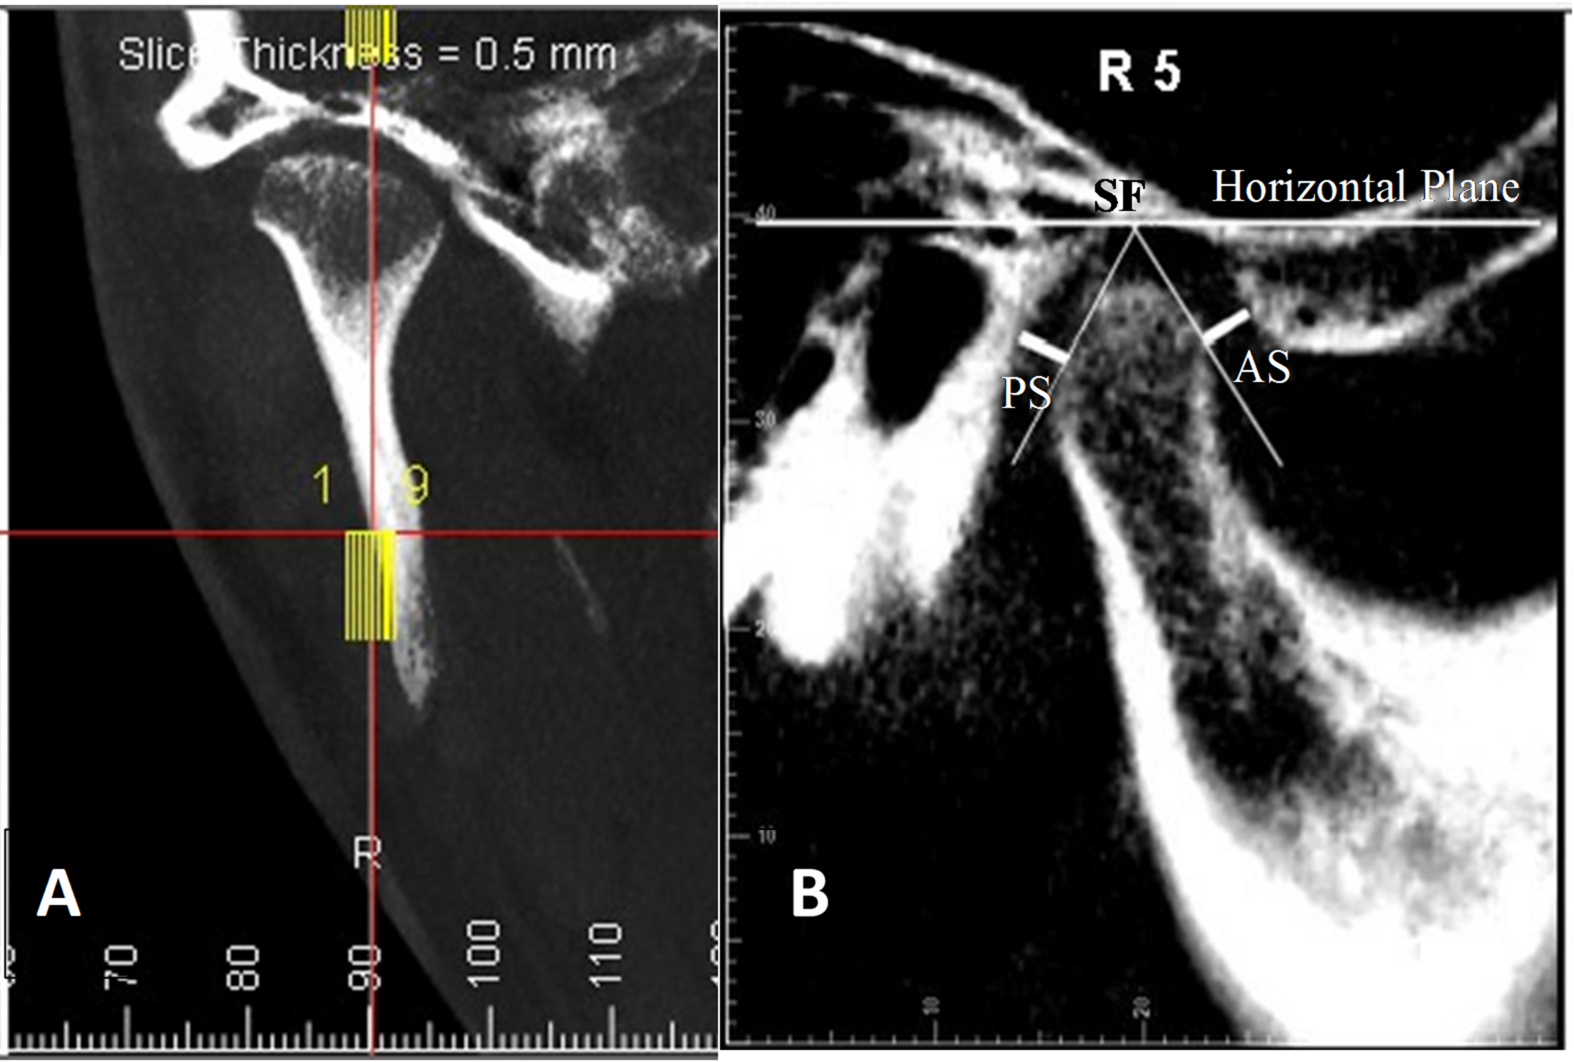

Fig. 3

(A) The glenoid fossa as seen in the coronal view, with its central part determined based on the vertical reference line. (B) The sagittal slice of the CBCT image of the mandibular condyle in the glenoid fossa. From the superior fossa (SF), lines were drawn tangent to the most prominent anterior and posterior surfaces of the condyle. The distances from these tangent points to the glenoid fossa were measured and recorded as the anterior joint space (AS) and posterior joint space (PS), respectively. The figure was produced using Dolphin Imaging software (Version 11.9, Dolphin Imaging, Chatsworth, CA, USA; https://www.dolphinimaging.com/).